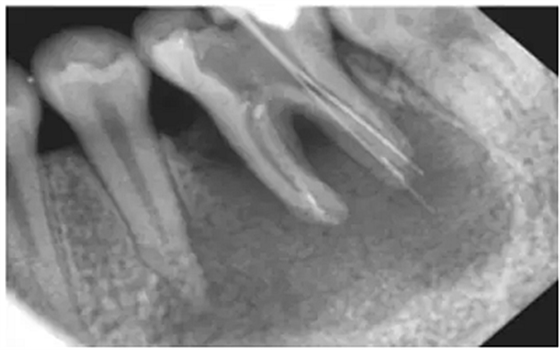

注:a.在鈣化細(xì)小/彎曲/形成臺(tái)階的根管,即使銼針未到狹窄區(qū),阻力也會(huì)明顯增大,導(dǎo)致感覺(jué)錯(cuò)誤;b.在根尖周組織破壞嚴(yán)重(陰影部分),有痛感時(shí),已明顯超出根管口。(如圖)

方法二:X光

采用X光拍片測(cè)量

優(yōu)點(diǎn):能觀察牙的全貌,尤其是牙冠和牙根的解剖形態(tài),冠根關(guān)系以及牙根的大小、形態(tài)和位置

缺點(diǎn):操作繁瑣、費(fèi)事、射線污染

1) 三維結(jié)構(gòu)投射在二維平面上,因投射角度不一樣,數(shù)據(jù)容易出錯(cuò)。

2)根尖孔不能體現(xiàn)在牙片上,而80%以上的根尖孔都不在牙齒根尖而是在側(cè)邊。

根尖開口在側(cè)邊時(shí),X線片投射引起長(zhǎng)度偏差錯(cuò)誤。

根尖開口距離牙齒根尖距離越大,誤差越大,會(huì)引起嚴(yán)重超充。